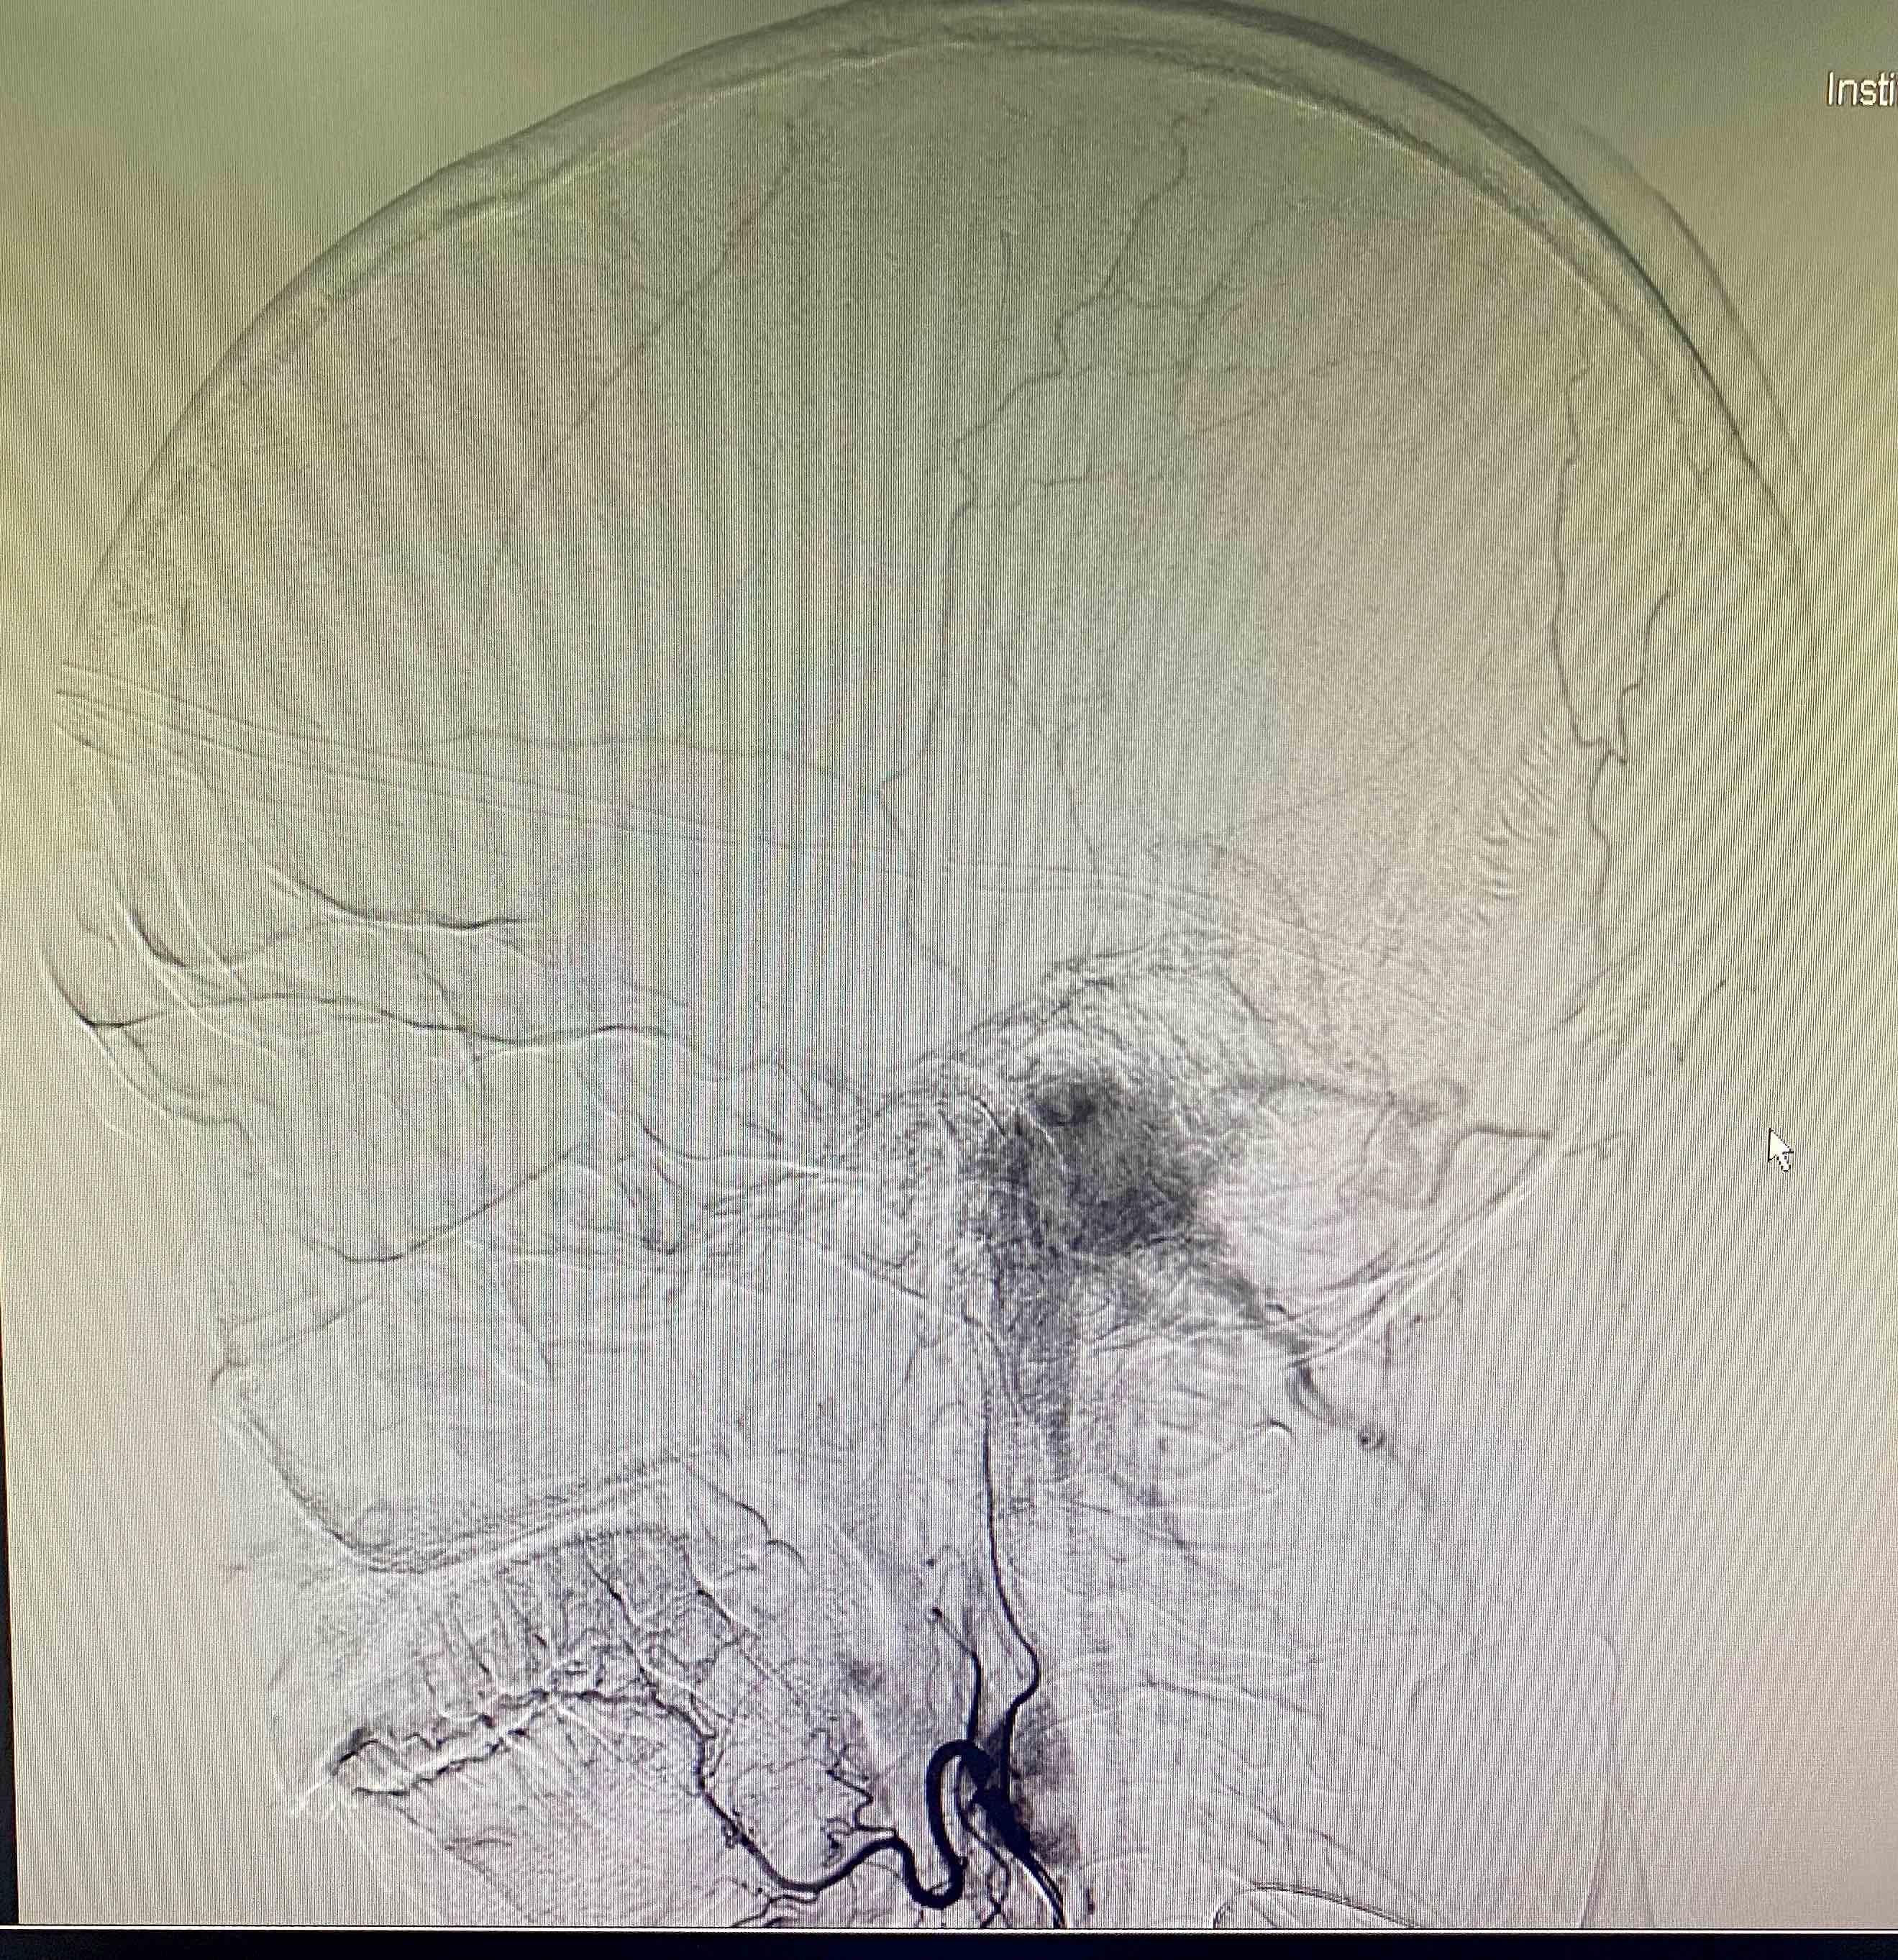

颈静脉孔区肿瘤是神经外科、耳鼻喉科和头颈外科的交界区病变。三国交界常常三不爱管。这个区域的鞘瘤和脑膜瘤可能还相对好做,但血供极其丰富的球瘤却有些麻烦,今天遇到一个中等大小球瘤,术前还是计划用神经外科的视角去处理这个病变,但为了能更好的暴露肿瘤边界以期整块切除控制出血。我们将乳突前方刚出茎乳孔的面神经先暴露出来,以便更快而安全的切除乳突尖。同时在保留半规管和外耳道完整性的前提下向前移位面神经垂直段以达到暴露肿瘤前界的目的,术中切除C-1横突,解除其对前方肿瘤的遮挡(不做椎动脉移位)。

中等大小的球瘤在完整暴露边界的前提下控制出血是可期的,过去我并不会完整暴露面神经垂直段在其下方的部分切除时由于是盲掏,常常带来大量出血,因此这次改变战略,使用经典的方法,看来经典之所以经典是有道理的。不过暴露肿瘤边界的过程所需时间却是切除肿瘤的2-3倍😭。暴露后明显感觉手发麻,背发酸,做颅底是真苦!